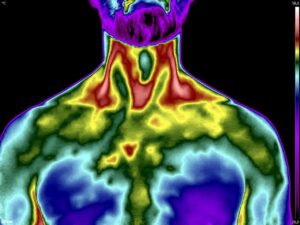

Como no caso dos termogramas abaixo de um paciente do sexo masculino, 44 anos, sem comorbidades e que apresentou dor em cervical. Foi realizado uma Análise Termofuncional e detectado alterações térmicas condizentes com o relato de dor.

Com estes achados foi possível determinar a cadeia postural que acometia o paciente, determinando o seu tratamento.

Somente com o conhecimento integral do Método de Termografia Infravermelha é possível detectar alterações e associá-las a uma disfunção.